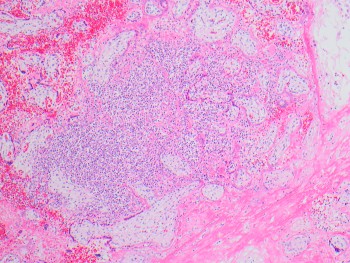

81-year-old female with a remote history of follicular lymphoma was undergoing evaluation for possible disease recurrence when an incidental right breast mass was identified.